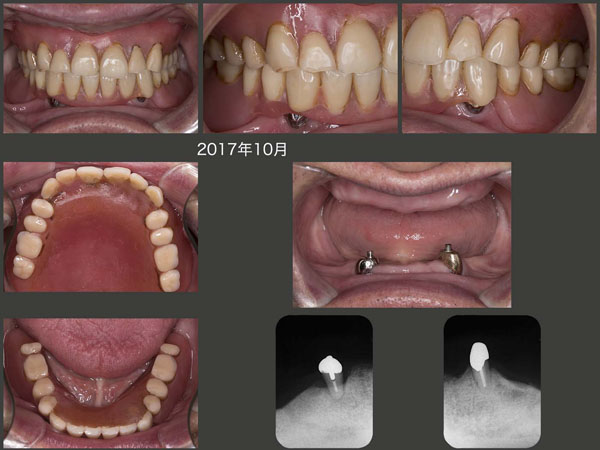

2017年6月,右下3が保存不可能となり抜歯することになった.ここで,この時を待っていた残根状の左上3を右下3部に移植することにした.(17年7月)なお左上5は,歯周ポケットが深くなったので抜去した.